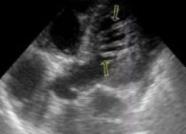

Основной метод диагностики дополнительной хорды левого желудочка — эхокардиография.

У некоторых пациентов с малыми сердечными аномалиями исследуют и другие органы. Обычно это необходимо при врожденных или наследственных болезнях соединительных тканей. Эхокардиография позволяет получить достоверные сведения об особенностях строения органа. Наиболее результативен метод при пролабировании клапанов. Трехмерная эхокардиография дает возможность оценить степень пролапсов заслонок, присутствие и степень регургитации, негативные изменения клапанных структур. Патологии хорд обнаружить труднее, для их диагностики применяют двухмерную эхокардиографию.

При ультразвуковом исследовании плотные хорды хорошо просматриваются. В заключении может быть указано «гемодинамически незначимая» или «гемодинамически значимая» хорда. В первом случае это никак не повлияет на работу органа и здоровье пациента. А вот со «значимой» хордой лучше дообследоваться у кардиолога.

Диагностирование

Дополнительная ткань в ЛЖ выявляется при проведении УЗИ сердца (для ребенка в возрасте одного месяца этот метод диагностики заменяется ЭХО-КГ). Исследование достаточно точное, процедура безболезненная. ЭХО-КГ (эхокардиография) направлена на изучение сердца в реальном времени и движении.

Доплеровский метод диагностики применяется для определения длины доп. нити, ее плотности, толщины, места крепления, скорости кровотока по ней и так далее.

Для того чтобы точно поставить диагноз – дополнительная хорда в левом желудочке сердца, врач назначает ультразвуковое обследование. Благодаря УЗИ, доктор может быстро, безболезненно и точно диагностировать сердечное заболевание или патологию. Кроме того, эхокардиография позволяет изучить сердце в реальном времени и в движении. Изучают проблемы дополнительной хорды и с помощью доплеровского метода, который помогает определить длину нити, её толщину, место крепления и скорость кровотока по ней.